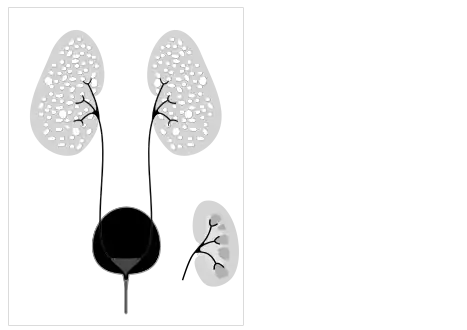

Ultrasonography is the primary method to evaluate autosomal recessive polycystic kidney disease, particularly in the perinatal and neonatal stages.[3]